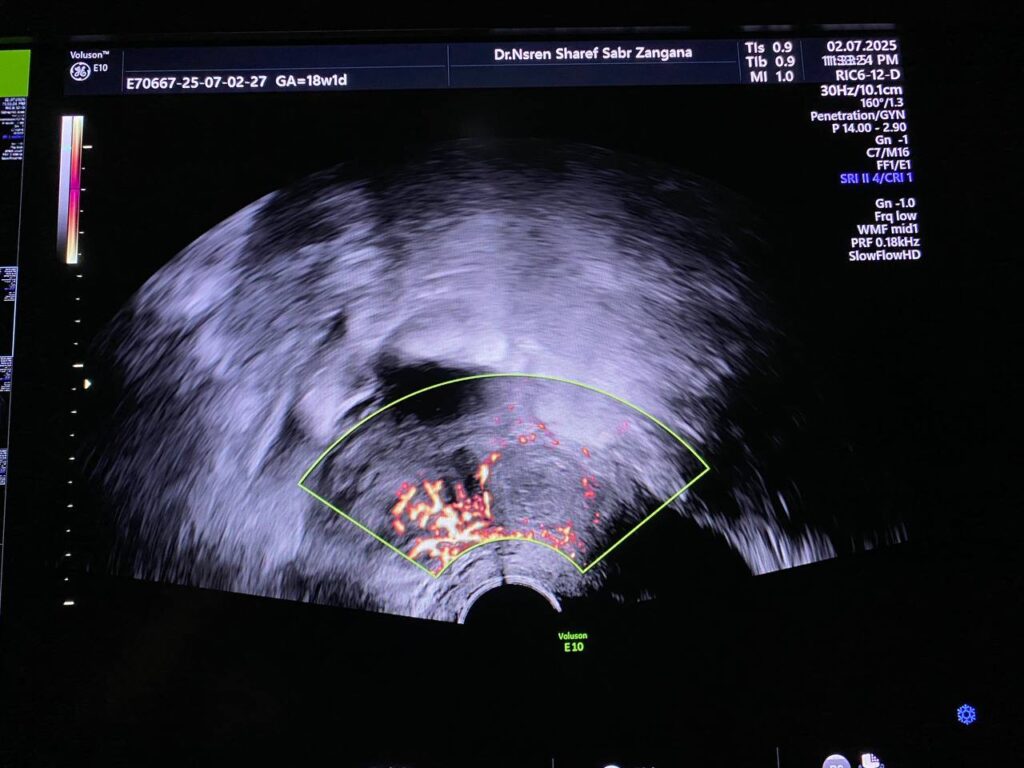

· Right ovary contain avascular circumscribed cystic mass 38x38mm , mostly physiological, for follow up